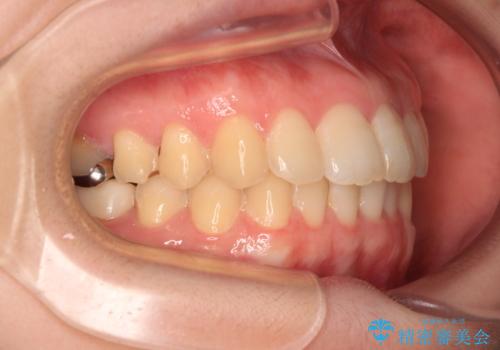

デコボコ歯列をきれいに インビザラインによる矯正治療

- 上下歯列全体のデコボコを気にして来院された患者様です。

主に下顎歯列全体の後方移動とIPR(歯と歯の間を削る)によってデコボコが解消するように設計し、インビザラインにより治療を行うこととしました。

1年半程度で終了するのではないかと予想しましたが、途中1年以上の来院がなく、トータルで3年の時間がかかってしまいました。

前歯のデコボコはより改善することが望ましい状態でしたが、患者様の希望により終了することとなりました。